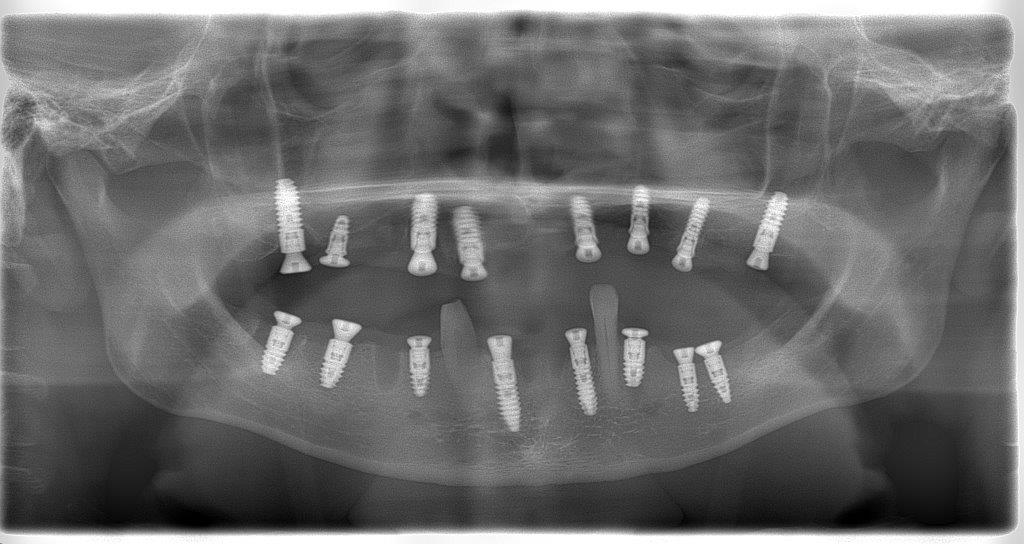

Исследование на рентгене после имплантации зубов

Раздел: Снимки-откровения